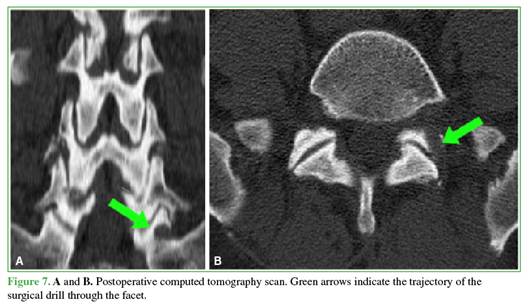

Under general anesthesia, the patient is placed in the prone position. Using direct anteroposterior fluoroscopy, the tip of the superior articular facet of S1 is identified and marked with a 16-gauge needle. An 8 mm skin incision is made and the lumbar fascia is opened. The working cannula and endoscope are advanced together. Lateral drilling of the inferior vertebral facet is performed using a diamond burr. As space is progressively created in the medial and ventral directions, the cannula is advanced. Once the anterior cortical bone of the facet is identified, it is resected using a 3 mm Kerrison rongeur. Fluoroscopic confirmation of the correct working direction is then performed (Figures 5-7).